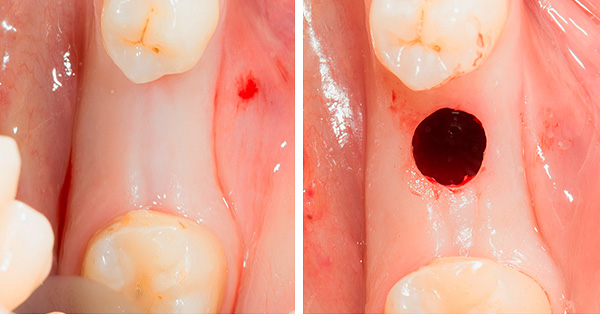

Quanto ao implante transgengival - se você ler os materiais publicitários, ele será realizado através da chamada "punção" das gengivas. De fato, a incisão mais verdadeira é feita na forma de um círculo com a ajuda de um mucótomo circular. Ou seja, embora o anúncio afirme que o implante não é cirúrgico e que, segundo eles, é realizado sem incisão, mas apenas por meio de uma "punção", no entanto, estritamente falando, há uma pequena operação com uma incisão circular nas gengivas.

Como observado acima, o implante transgengival de dentes é hoje posicionado por algumas clínicas como a tecnologia de instalação de implantes dentários sem cortar as gengivas, ou seja, através de uma punção na mucosa. O que é essa "punção", já descobrimos - na realidade, na realidade, uma punção é chamada de incisão circular da gengiva usando um mucótomo.

Em contraste com a técnica clássica, durante o implante transgengival, as lesões dos tecidos moles são menos significativas - a incisão parece muito clara, quase o diâmetro da gengiva anterior instalada no pilar do implante. Ou seja, um "implante sem cirurgia" é, obviamente, um mito e uma manobra publicitária, mas com um mínimo de trauma no tecido gengival, a implantação é bem possível.

- Um corte circular é realizado ("punção");

- O furo se expande para o diâmetro desejado e se aprofunda;